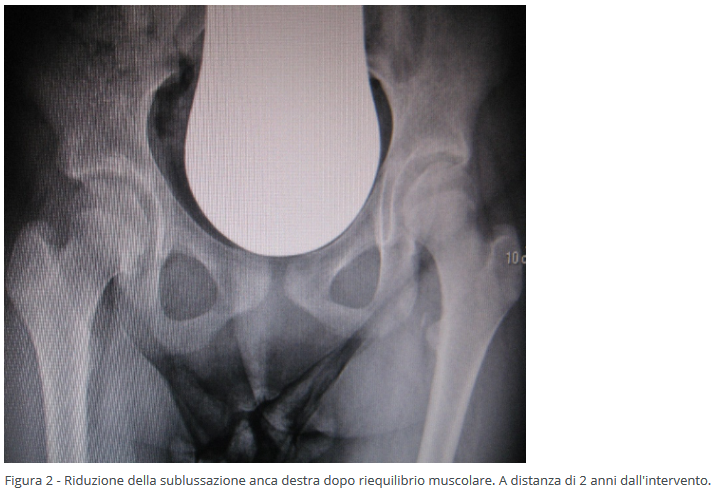

Il vantaggio del riequilibrio muscolare è quello di fermare o rallentare i danni causati dai muscoli spastici che, con le loro forze eccessive, conducono la testa del femore fuori dalla cavità acetabolare. Questo intervento si può eseguire anche in età molto precoce (2-3 anni) (Figure 1-2).